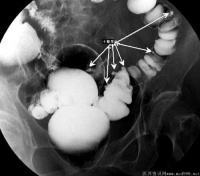

结肠憩室是指肠粘膜经肠壁肌层缺损处向外形成囊状突出的病理结构。多个憩室的存在则称之为结肠憩室病

憩室绝大多数为后天形成的,多位于乙状结肠盲肠升结肠也不少见。